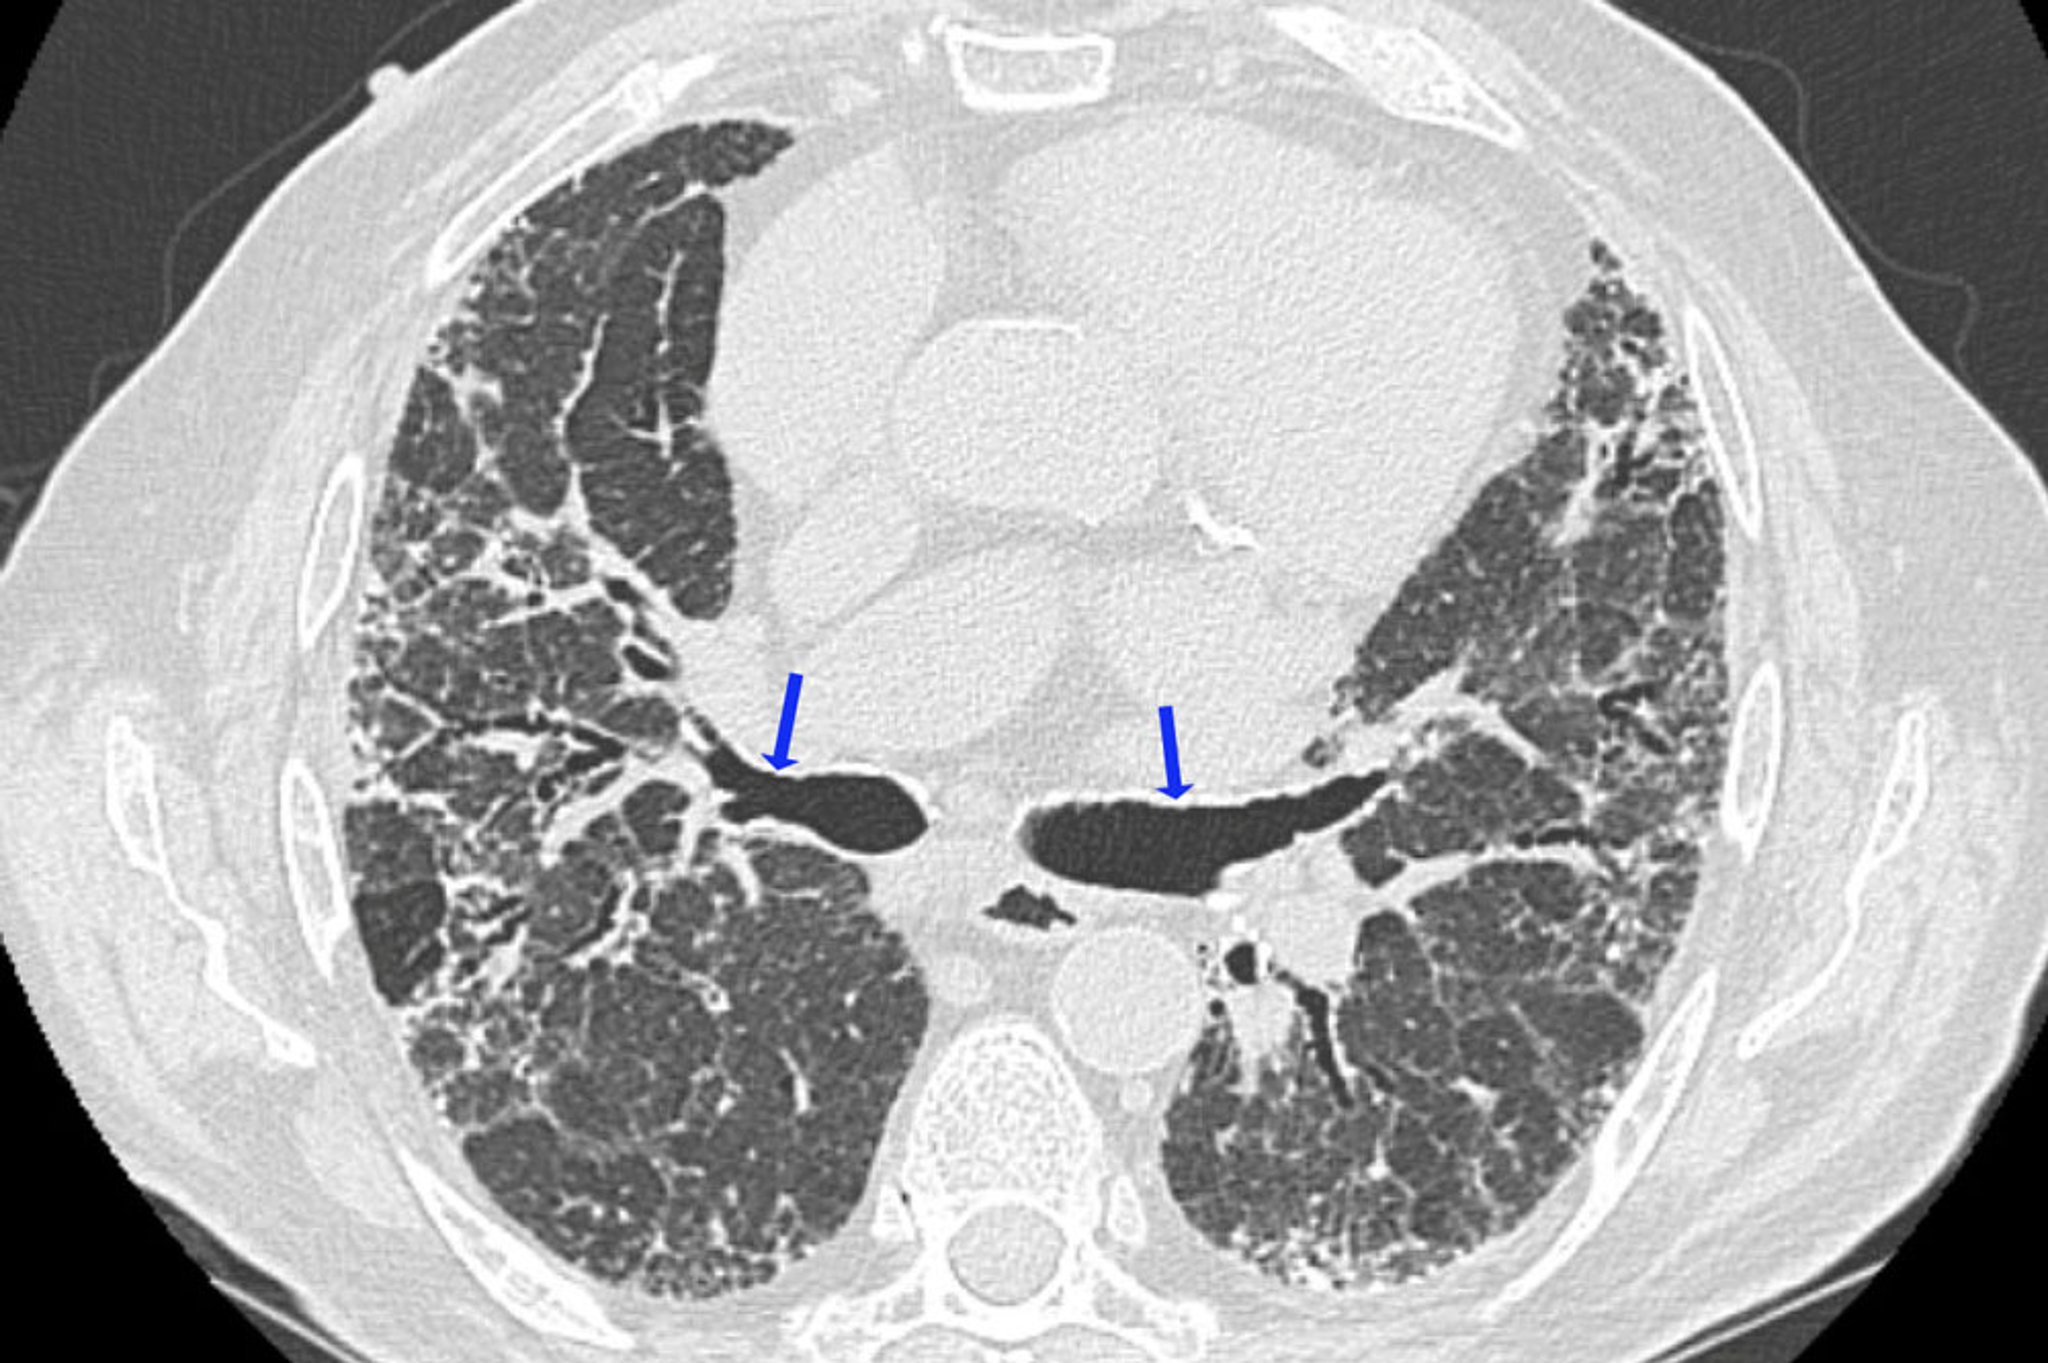

Neumonitis crónica por hipersensibilidad

Esta TC de alta resolución muestra hallazgos de fibrosis, incluyendo reticulación irregular y bronquiectasias por tracción (flechas). Las áreas pulmonares hipodensas son compatibles con regiones de obstrucción de la vía aérea. Esta combinación de hallazgos sugiere neumonitis por hipersensibilidad.

Image courtesy of Joyce Lee, MD, MAS.